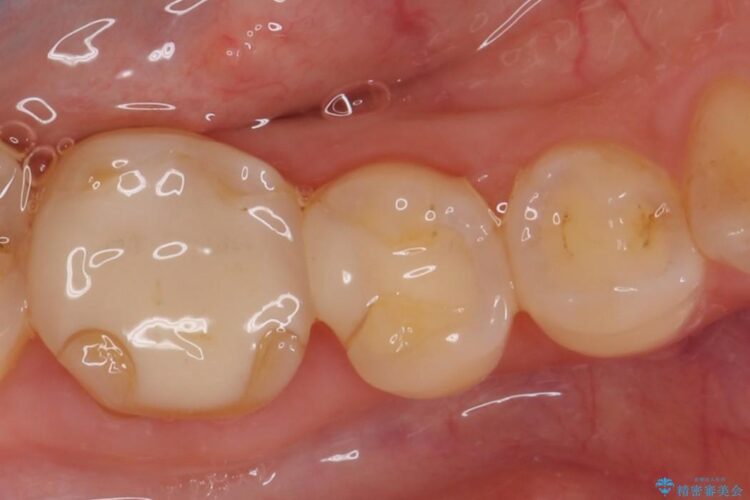

ぱっと見ただけでは特に問題ないように見えますが、レントゲンをよく確認すると詰め物と歯の間に隙間がはっきりと確認ができます。

隙間が発生しているインレー(詰め物)